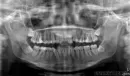

Мне 24, и я решила установить брекеты. Но проблема в том, что все три шестых зуба у меня мертвые. Врач предлагает удалить шестые, но почему-то не хочется потом жевать только семерками и пятерками.

И вот дилемма: удалить шестерки мертвые или четверки? Мне интересно, какое мнение у стоматологов в этом случае?